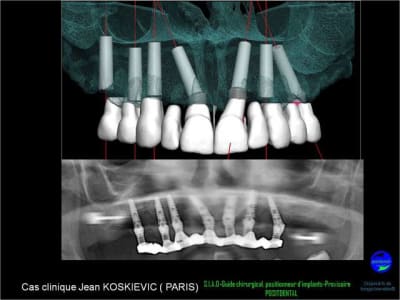

projet implantaire pour février

1er étape le wax-Up, dans ce cas clinique il est réalisé en 3D

guide de positionnement et intrado du bridge provisoire